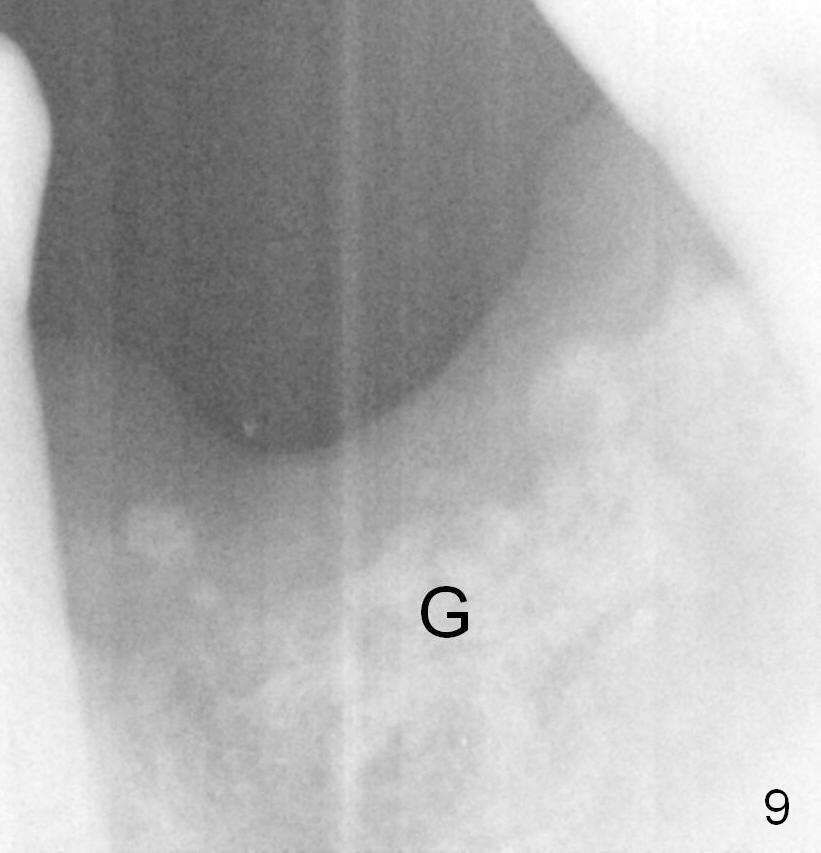

After debridement, socket preservation is accomplished with allograft and Osteogen, covered with Collagen plug (Fig.9).